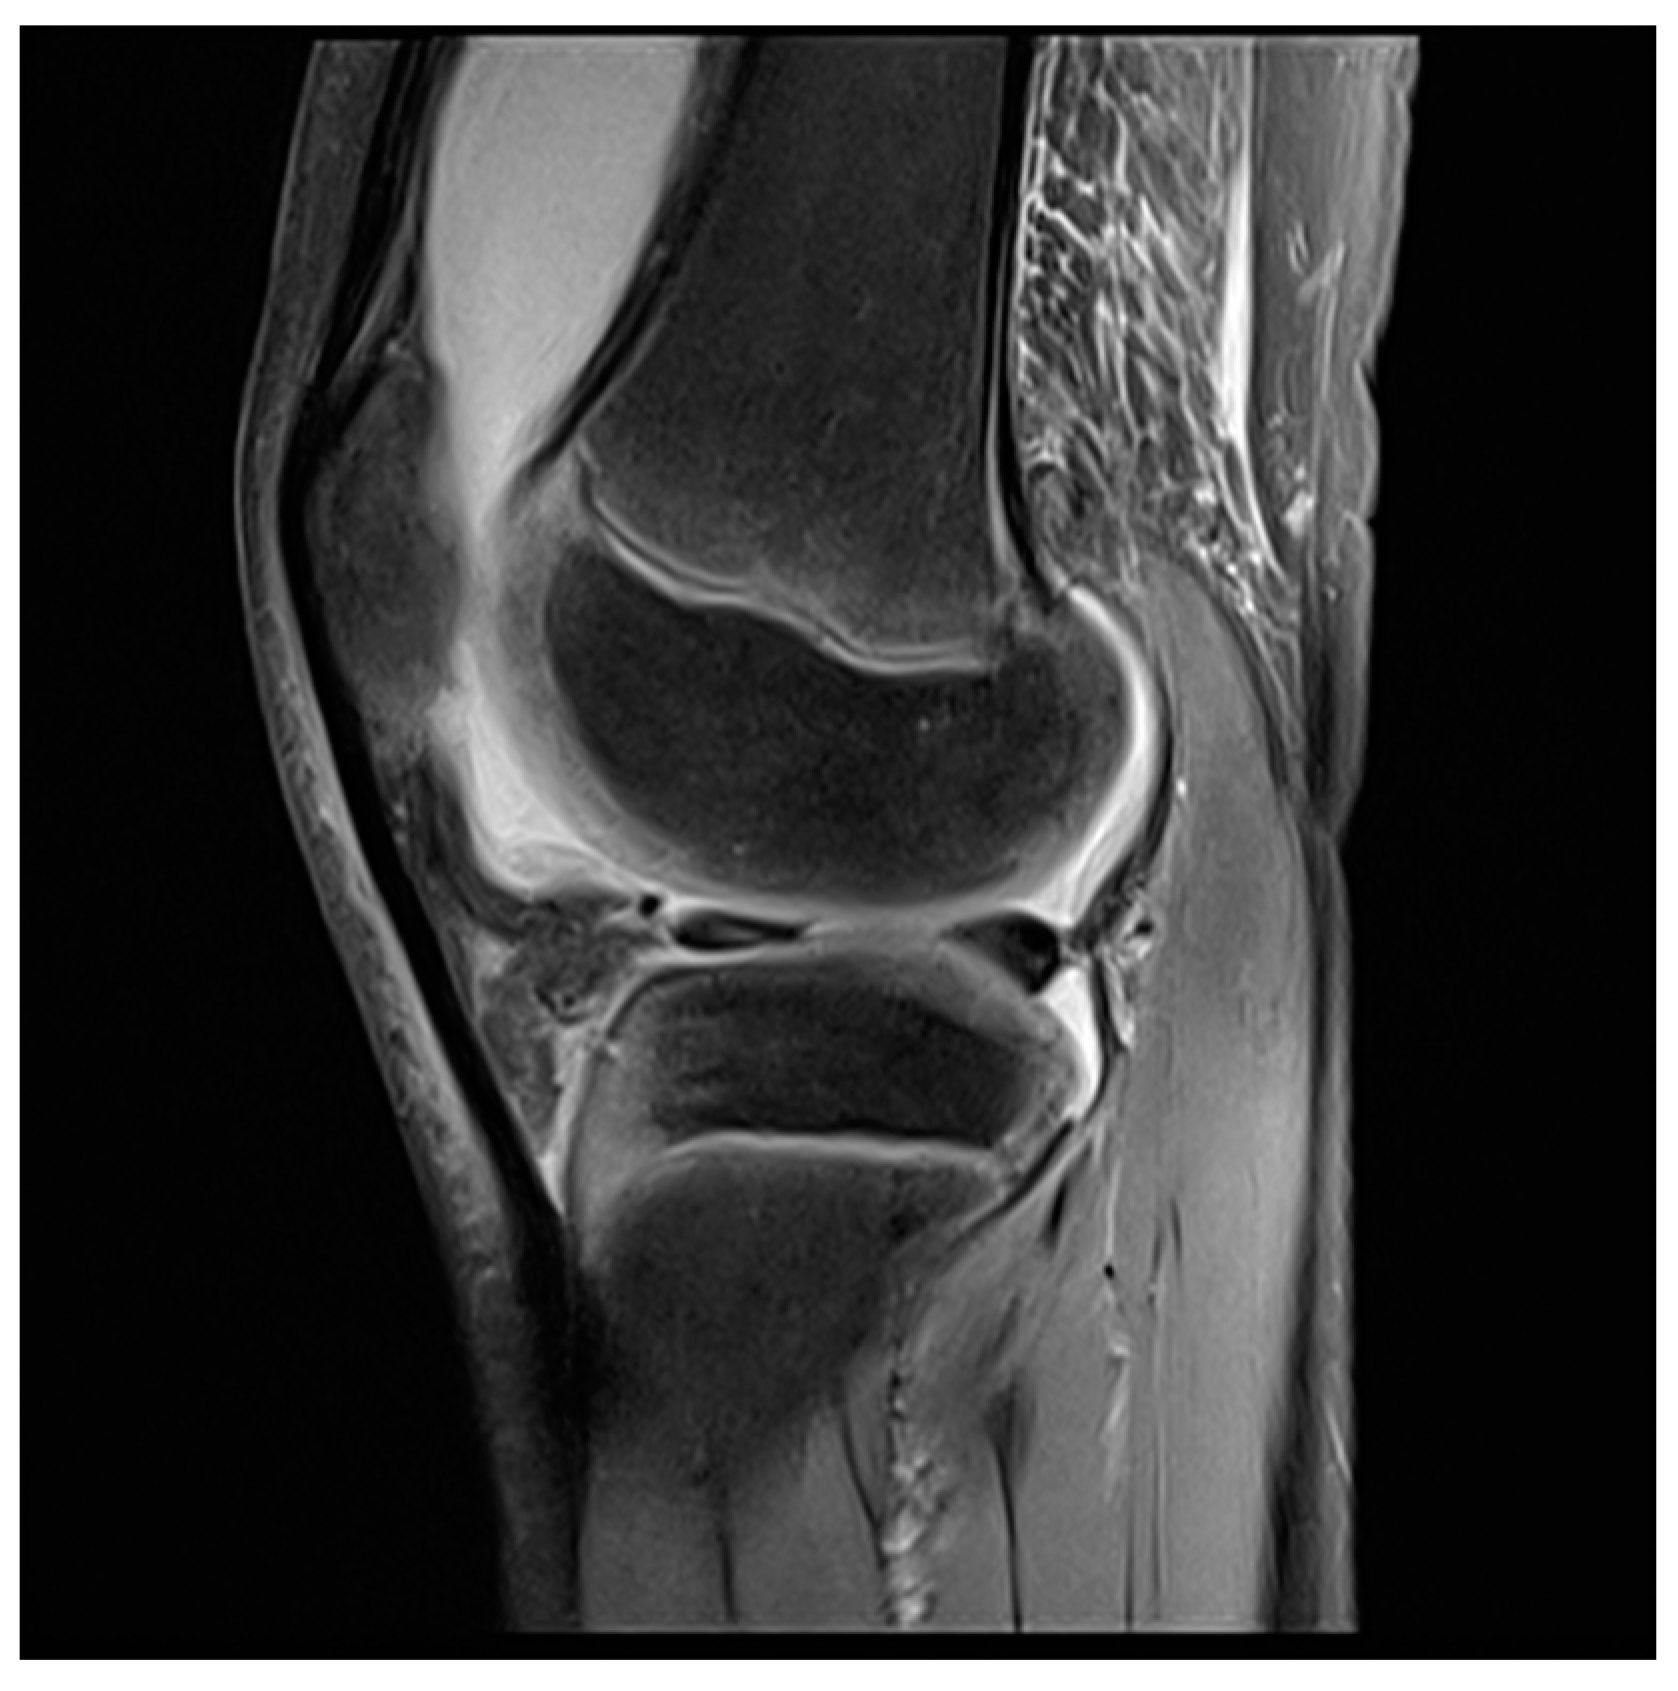

- Hirose, J.; Nishioka, H.; Tsukano, M.; Matsubara, S.; Usuku, K.; Mizuta, H. Matrix changes in articular cartilage in the knee of patients with rheumatoid arthritis after biological therapy: 1-year follow-up evaluation by T2 and T1ρ MRI quantification. Clin. Radiol. 2018, 73, 984.e911–984.e918. [Google Scholar] [CrossRef]

- Maderbacher, G.; Greimel, F.; Schaumburger, J.; Grifka, J.; Baier, C. The knee joint in rheumatoid arthritis-current orthopaedic surgical treatment options. Z. Rheumatol. 2018, 77, 882–888. [Google Scholar] [CrossRef] [PubMed]

- Carl, H.D.; Gelse, K.; Swoboda, B. Total knee arthroplasty for rheumatoid arthritis. Z. Rheumatol. 2011, 70, 411–416. [Google Scholar] [CrossRef]